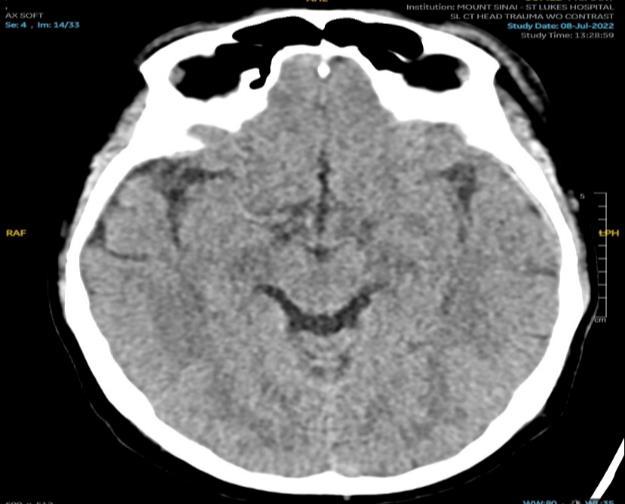

VALACYCLOVIR ASSOCIATED NEUROTOXICITY IN A PATIENT WITH END STAGE RENAL DISEASE

Venus Sharma1 , Rohit Rajesh Nathani1 , Ayush Gandhi1

1Mount Sinai Morningside-West Hospitals, Icahn School of Medicine at Mount Sinai, New York, NY, United States

TRENDS IN SCREENING AND PREVENTION OF ANORECTAL AND COLON CANCER IN TRANSGENDER PEOPLE

63

Shabari Mangalore Shenoy1, Shanique Wilson Noack1,2, Emily Seltzer1 , Omar Belfaqeeh1, Patricia Miguez Arosemena1, Emilia Bagiella3, Amreen Dinani3 , Ilan Weisberg2, Joshua D. Safer3